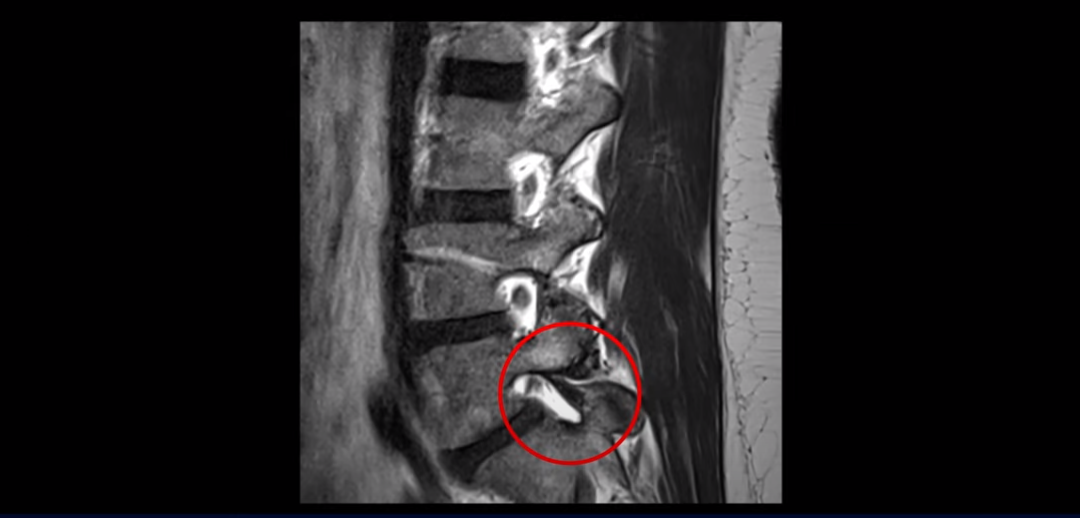

그런데 이 환자분의 X-ray를 보면 척추분리증으로 인한 전방전위증과 불안정성이 있습니다.

허리를 구부렸다 폈다 할 때 허리 신경 공간의 변화가 있음을 유추해 볼 수 있습니다.

그러나 전방전위증이 조금 있다는 이유만으로 섣부르게 나사 박는 유합술까지 하기에는 수술 예후가 불확실하니 환자분은 너무 불안해 하셨습니다. 그래서 열심히 인터넷과 유튜브를 뒤져 저희 병원을 찾아보시고 전화를 주신 건데요. 전화 상담 결과 마비가 발생한지 얼마 되지 않았다는 점, 또 무거운 걸 들다가 허리 통증, 다리 방사과 함께 찾아온 마비 증상이라 허리 문제일 가능성이 매우 높다는 점, 이런 이유로 저희 비수술 치료로 마비가 회복될 가능성이 높다는 것을 설명해 드렸고 서울로 올라와서 입원 치료 받으시라고 권유해 드렸습니다.